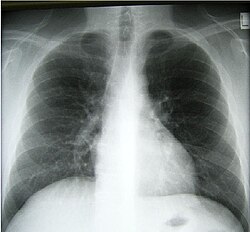

[sửa | sửa mã nguồn]Trong con người, phổi gồm có hai buồng phổi nằm bên trong lồng ngực, được bao bọc bởi các xương sườn chung quanh, phía dưới có cơ hoành ngăn giữa phổi và các cơ quan trong bụng như gan, dạ dày, lá lách. Giữa hai buồng phổi là khí quản (1) - là ống dẫn khí chính. Khí quản phân ra hai nhánh phế quản chính (2) (3). Quả tim nằm giữa hai phổi (trung thất), hơi trệch về bên trái.[1][2]

Buồng phổi bên trái có 2 thùy (trái-trên (5a), trái-dưới (5b)), bên phải có 3 thùy (phải-trên (4a), phải-giữa (4b) và phải-dưới (4c)). Mỗi buồng phổi có một phế quản chính, một động mạch (8) và hai tĩnh mạch - những ống dẫn này chia như nhánh cây chi chít từ lớn ở giữa ngực (trung thất) đến cực nhỏ phía ngoài cùng của buồng phổi - kèm theo là các dây thần kinh và mạch bạch huyết.